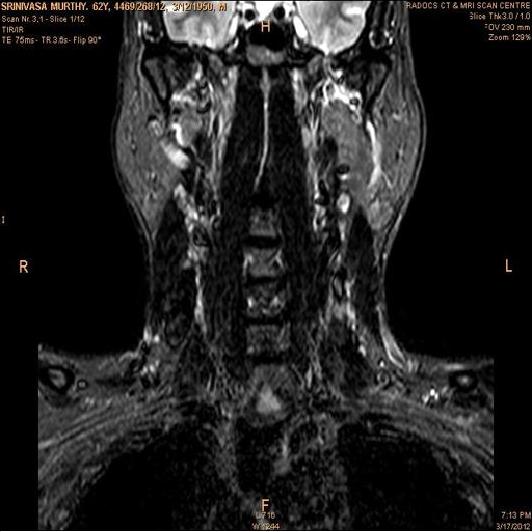

The developed algorithm presented in the previous section was coded using Matlab Version 8.0. The experiment was conducted by considering poor quality spinal cord images of having various lesions. The first column of Fig. 4 shows the axial view of neck spinal cord images of size pixels, respectively. The second column of Fig. 4 presents the same images enhanced using histogram equalization. As is evident from the results presented, the histogram equalization method performs global image enhancement operation which improves the contrast of an image but at the cost loss in image details. The third column of Fig. 4 shows the MSR based spinal cord image enhancement. It can be seen that from the result presented, MSR scheme improves the details that are not clearly visible in histogram equalization technique. In general, image enhancement achieved by MSR method is better compared to histogram equalization. However, the MSR method voilates gray world assumption. Therefore, the image enhanced by this scheme appears to be grayish. Although, numerous work have been reported for solving the problem due to gray world voilation, no work seems to developed for complete elimination.

The fourth column of Fig. 4 shows the image enhanced using Chao et al. []. It can be seen from the results presented that the reconstructed images of Chao’s method have black spots. The appearance of these dark patches degrades the visual quality of the enhanced image. The image enhanced using proposed multirate multiscale retinex image enhancement method presented in the fifth column of Fig. 4, overcomes the drawback of the Chao’s method. As we can see from the simulation results, image enhancement achieved by the proposed method has improved details with significant contrast enhancement. The enhanced images from the proposed method provides information to physicians, radiologists and researchers for various types of pathology detection.